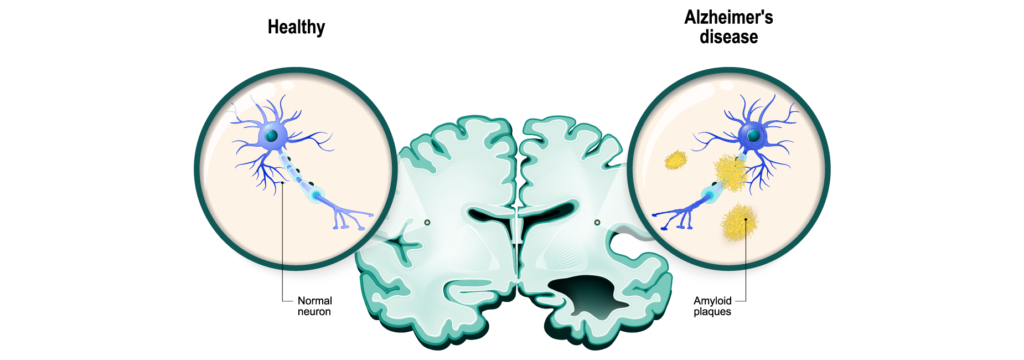

Alzheimer’s disease is the commonest form of dementia worldwide, accounting for about 60-80% of cases. It is caused by the abnormal build-up of proteins in the brain cells known as tau protein as well as around the cells called amyloid plaques. These abnormal proteins causes disruption in neurochemical transmission between brain cells and accelerates brain cell death. The disease process frequently causes shrinkage of the hippocampus of the brain, which is responsible for memory storage, and gradually spreads to all areas of the brain.